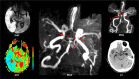

Fetal-type or fetal posterior cerebral artery (FPCA) is a variant of cerebrovascular anatomy in which the distal posterior cerebral artery (PCA) territory is perfused by a branch of the internal carotid artery (ICA). In the presence of FPCA, thromboembolism in the anterior circulation may result in paradoxical PCA territory infarction with or without concomitant infarction in the territories of the middle (MCA) or the anterior (ACA) cerebral artery. We describe 2 cases of FPCA and concurrent acute infarction in the PCA and ICA territories-right PCA and MCA in Patient 1 and left PCA, MCA, and ACA in Patient 2. Noninvasive angiography detected a left FPCA in both patients. While FPCA was clearly the mechanism of paradoxical infarction in Patient 2, it turned out to be an incidental finding in Patient 1 when evidence of a classic right PCA was uncovered from an old computed tomography scan image. Differences in anatomical details of the FPCA in each patient suggest that the 2 FPCAs are developmentally different. The FPCA of Patient 1 appeared to be an extension of the embryonic left posterior communicating artery (PcomA). Patient 2 had 2 PCAs on the left (PCA duplication), classic bilateral PCAs, and PcomAs, and absent left anterior choroidal artery (AchoA), suggesting developmental AchoA-to-FPCA transformation on the left. These 2 cases underscore the variable anatomy, clinical significance, and embryological origins of FPCA variants.